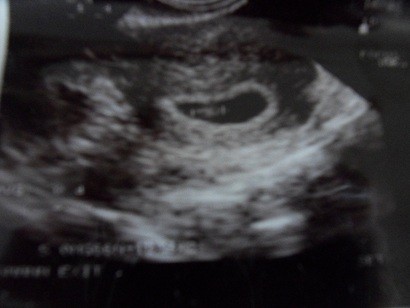

Aśka - w pęcherzyku bardzo ładnie widać ciałko żółte, a jak jest ciałko żółte to i na pewno jest tam schowany zarodek :-) ... masz fajny kształt pęcherzyka, od razu pomyślałam że wygląda jak banan

... może fasol będzie lubiał owoce